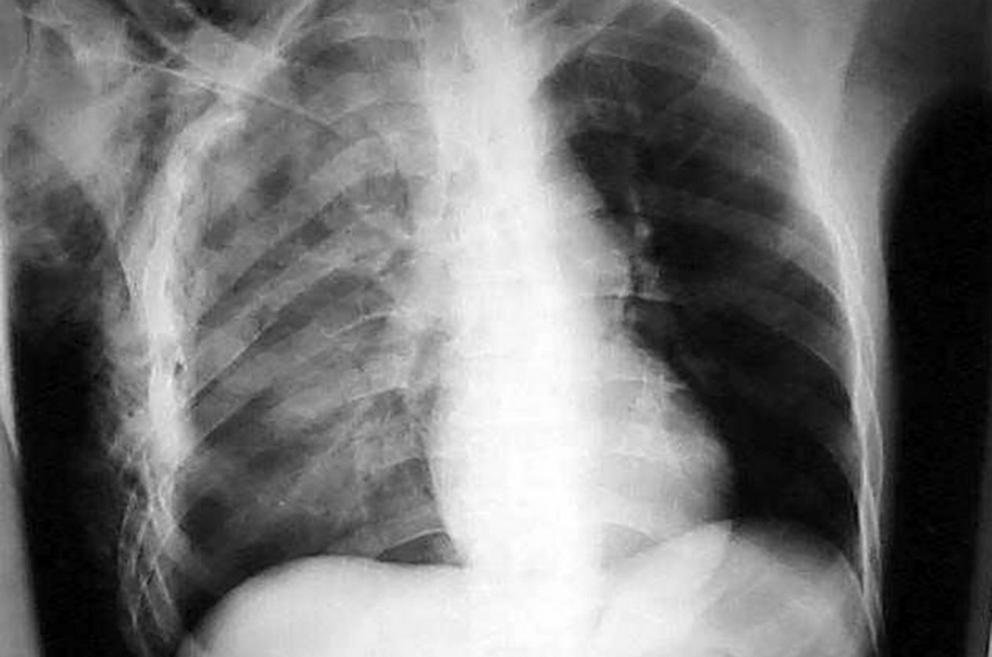

Инцидент произошел в Карасайском районе, где 12 января в своем доме скоропостижно скончался один из местных жителей. При проведении судебно-медицинской экспертизы у 28-летнего мужчины обнаружили тупую травму грудной клетки со множественными переломами ребер и ушиб легких, что могло стать причиной его смерти. Несмотря на то что родные потерпевшего не обращались с заявлением в полицию, по данному факту было возбуждено дело. Его расследуют по части 3 статьи 106 Уголовного кодекса Казахстана («Умышленное причинение тяжкого вреда здоровью, повлекшее смерть»).